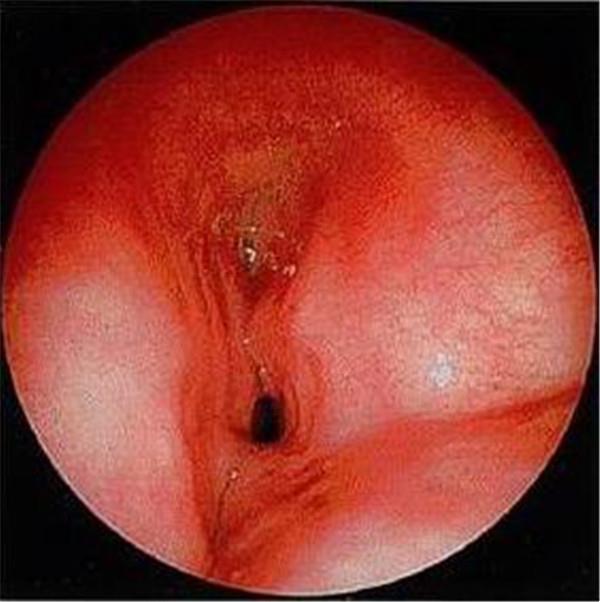

常見(jiàn)的鏡下改變:

喉裂

聲門(mén)下狹窄

氣道食管瘺

氣道狹窄